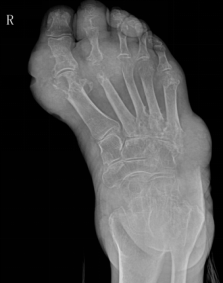

类风湿性关节炎

多发性、非特异性慢性滑膜炎症为主要表现的全身性疾病

多见于20-40女性

受累关节多呈对称性,以手足小关节为主

影像表现:①关节软组织肿胀;②关节间隙变窄、关节面边缘骨侵蚀;③软骨下多发囊样透亮区;④骨质疏松;⑤ 关节畸形和关节强直

F,55Y